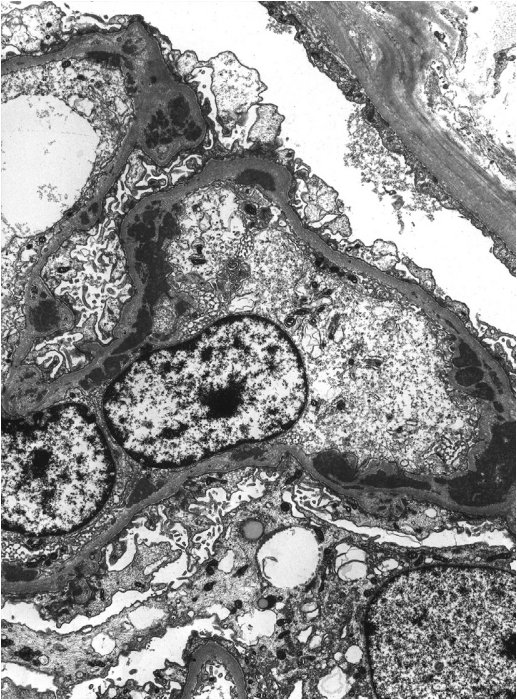

Ⅲ、Ⅳ型:由于系膜区、内皮下免疫复合物沉积,毛细血管内及系膜细胞增生,内皮细胞管网状包涵体结构(对高干扰素水平的反应)。可能存在分散的上皮下沉积物,涉及小于一半的肾小球和小于一半的毛细血管袢。如果大多数肾小球和毛细血管袢显示上皮下沉积,应诊断合并膜性LN(Ⅴ型)。沉积物可能表现出“指纹”样亚结构组织。

Ⅴ型:上皮下沉积,涉及一半以上肾小球毛细血管袢,伴有系膜沉积,偶有内皮下沉积。管网状包涵体可在内皮细胞的胞浆中。

狼疮型肾炎Ⅳ型(弥漫性LN),伴有上皮下和内皮下沉积。在这张图中没有显示系膜沉积。(电镜)